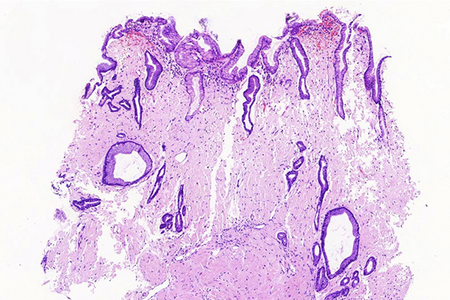

Histologically, lamina propria of gastric mucosa was expanded with amorphous paucicellular stromal deposits with cracking artifacts (Panels A and B). These depositions stained red with Congo Red stain (Panel C) and demonstrated characteristic apple-green birefringence in polarized light (Panel D). No malignancy was observed. Consequently, the final diagnosis was gastric amyloidosis.

Due to recurrent gastrointestinal bleeding and significant involvement of the stomach with amyloidosis, a distal resection of stomach was performed. Histological findings (Panel E) in the resection specimen, including Congo Red stain (Panel F) were similar to those described in the pre-operative biopsy.